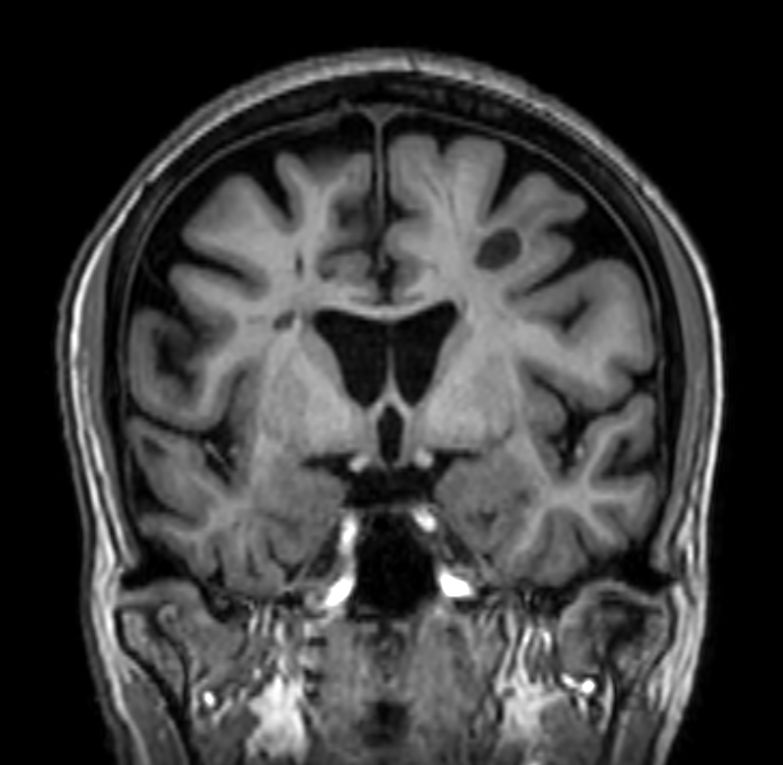

3D Double IR BrainVIEW (reformat) Compressed SENSE